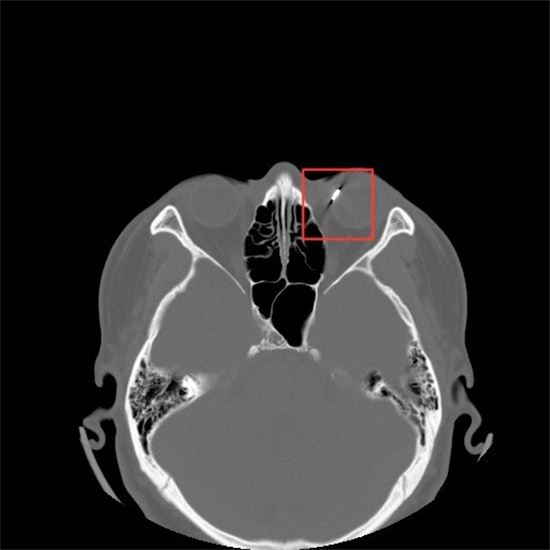

接诊的傅燕芳医生迅速为小王进行了初步检查,立刻意识到情况严重。通过精密设备和急诊CT检查,傅医生发现小王的左眼角膜上不仅有一道长约8mm的裂口,更糟糕的是,眼内的“高密度”异物已经贯穿了眼球前部,镶嵌在眼球后壁。

CT检查结果

术中诸主任缝合了破损的角膜,吸除了因损伤导致混浊的晶状体,并从眼内取出了一枚0.5×0.3×0.2cm的肾形铁片,比常人的瞳孔还要大!